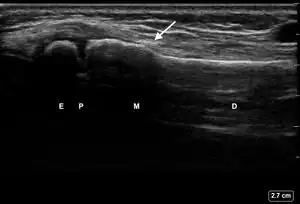

| 2 | Obtain, label, and save an image of the epiphysis (E), physis (P), metaphysis (M), and diaphysis (D). | ![]() | |